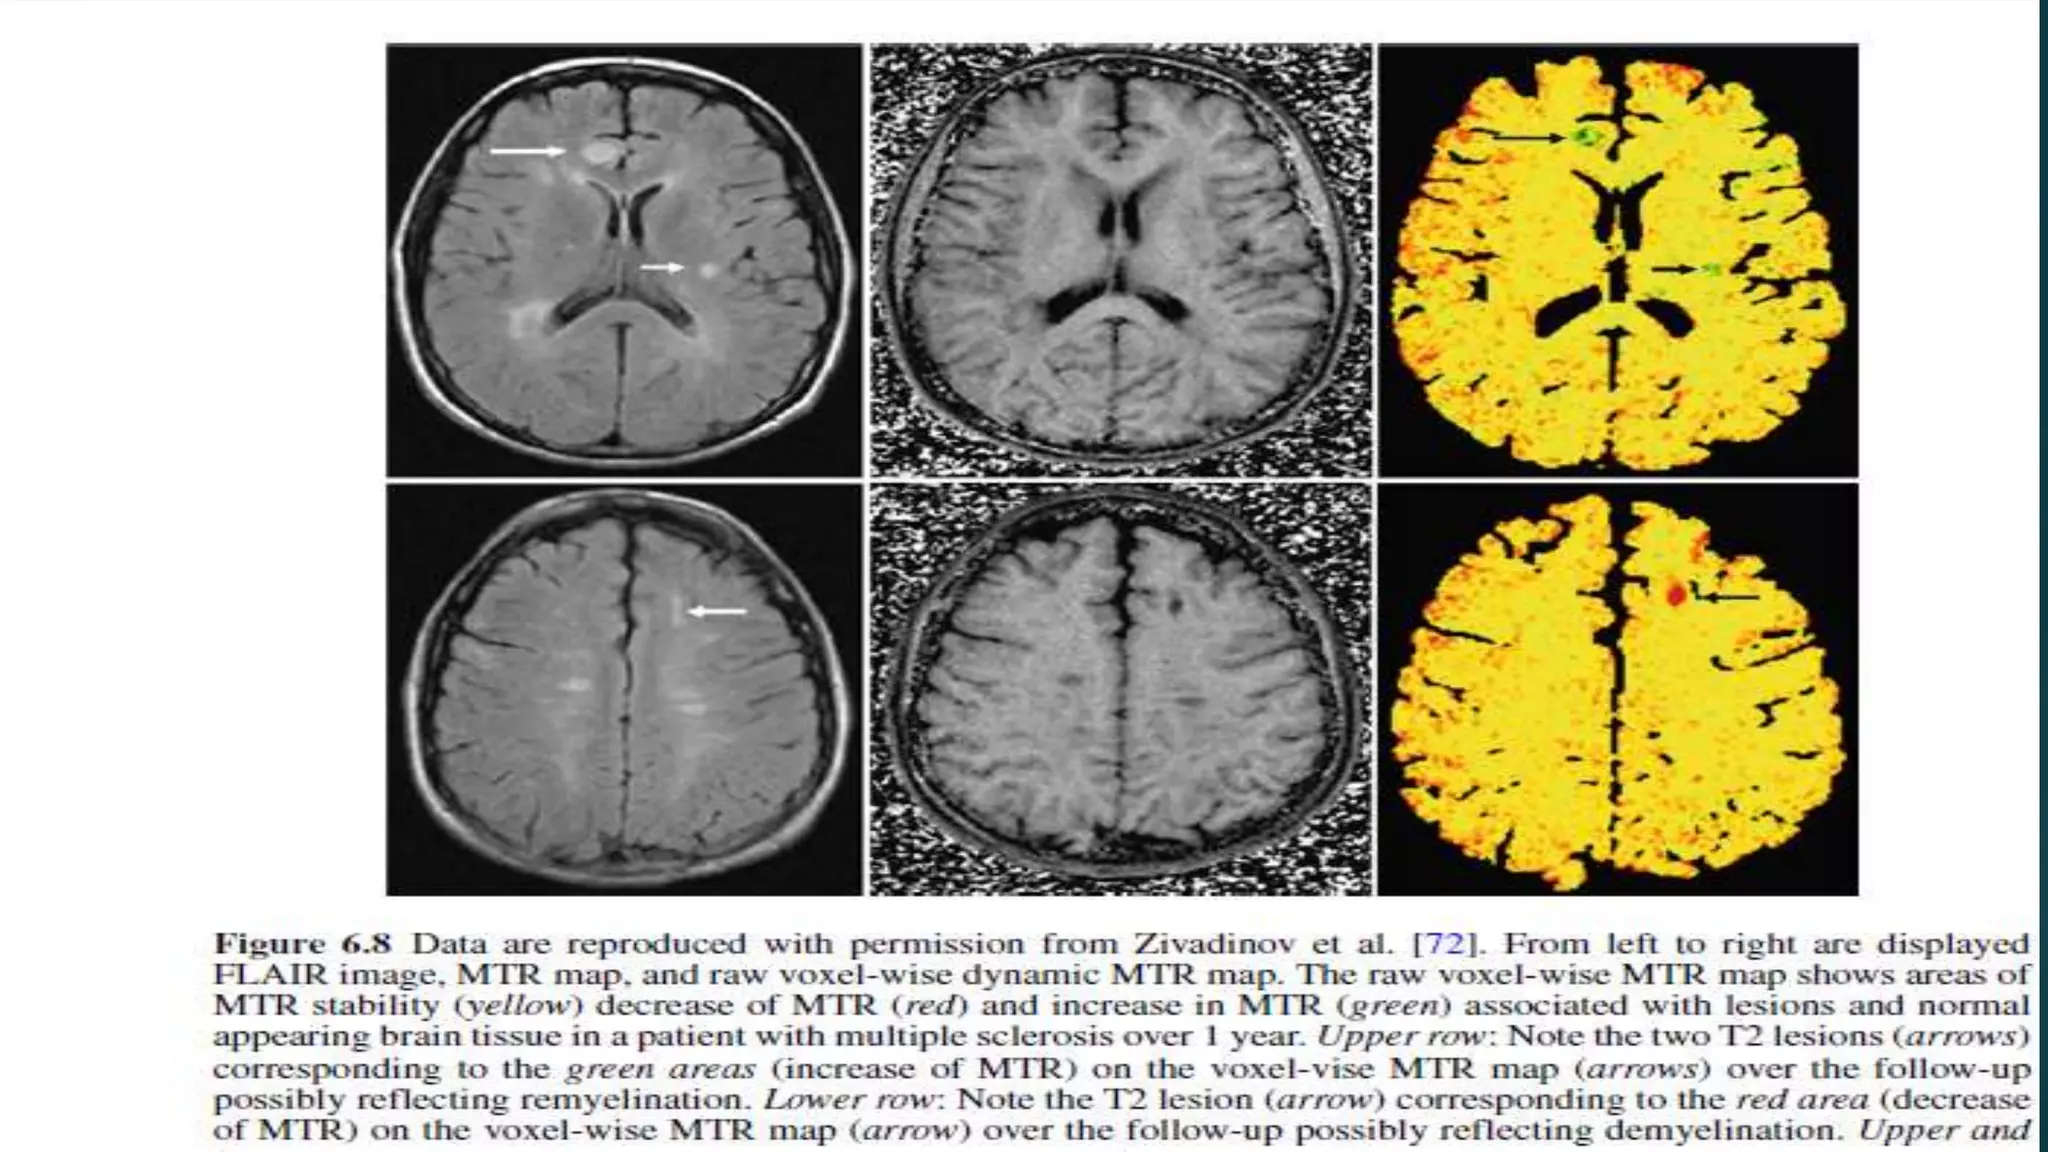

Magnetization Transfer Imaging Demyelinationis visualized as a reduced proton exchange, or a decrease in the magnetization transfer ratio (MTR), whereas an elevated proton exchange, or increased MTR, is evidence of possible remyelination or resolution of edema.

• 57.